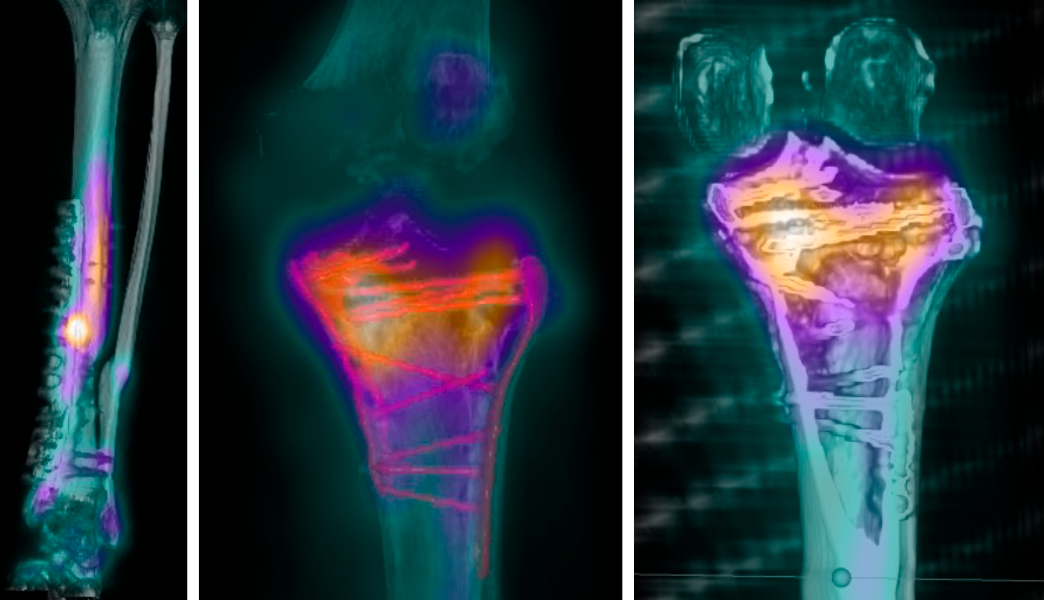

Infección ósea/Osteomielitis

Es una infección en el hueso que puede ocurrir tras fracturas, cirugías o heridas cerca del hueso causada generalmente por bacterias. Es más frecuente en personas con sistema inmunitario debilitado, con diabetes, con fracturas abiertas (que comunican el hueso con el ambiente exterior), o tras cirugías.

Suele requerir un tratamiento oportuno combinado de antibióticos y cirugía (limpieza quirúrgica, estabilización ósea mediante extracción, recambio o retención del material de osteosíntesis, reconstrucción ósea en caso de defectos), requiriendo individualizar cada caso.